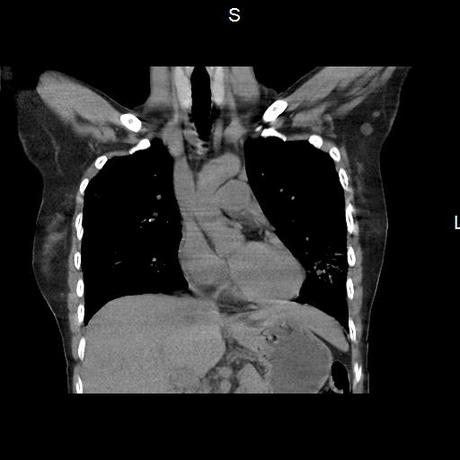

Se realiza volumen de tórax en fase simple, desde los opérculos torácicos hasta los hemidiafragmas, observándose:

El parénquima pulmonar con areas parcheadas difusas en vidrio despulido combinadas con otras areas hipodensas de baja atenuación debidas a atrapamiento aéreo y engrosamiento intersticial y zonas de fibrosis de predominio en lóbulos medios e inferiores de ambos pulmones.

- LOS HALLAZGOS PUEDEN ESTAR EN RELACIÓN A NEUMOPATIA INTERSTICIAL PROBABLE ETIOLOGIA HIPERSENSITIVA VS AUTOINMUNE/BACTERIANA/FUNGICA.